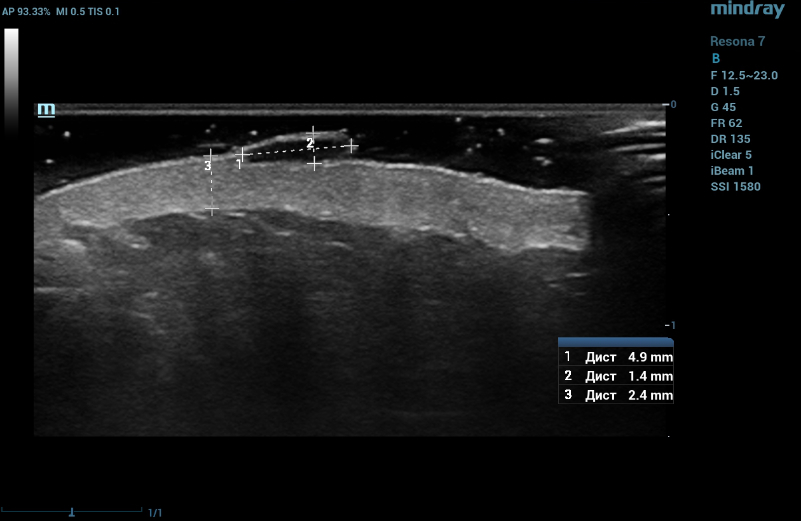

Ultrasound examination of the nevus was performed on the Resona 7 ultrasound machine (Mindray, China) using the high frequency linear transducer L20-5U. When the transducer is placed in the projection of the visible nevus of the left lateral surface of the anterior abdominal wall, an anechogenic oval-shaped mass, located under the epidermis, significantly protruding above the surface and deforming the epidermis outward, with clear even bounds, homogeneous echogenicity, without spreading into the dermis in depth, is visualized. The dermis is homogeneous with increased echogenicity (Figure 5). Blood flow is not registered inside the nevus in the Color Doppler mode (Figure 6).

Ultrasound examination of the nevus in B mode. Echo-signs of congenital nevi. The dermis is homogeneous with increased echogenicity

Figure 5. Ultrasound examination of the nevus in B mode. Echo-signs of congenital nevi